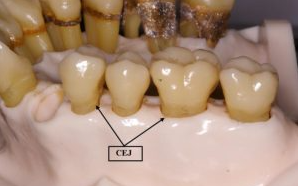

출처 : ASK A DENTIST

일반적으로 CEJ 라고 불리우는 치아의 머리와 뿌리의 경계에 이르는 만큼 잇몸뼈 높이가 유지되고 있어야만 하지만, 만성치주염으로 인해 잇몸뼈가 소실되면 이 높이를 잃어버리게 되고 왠만한 것은 치과용 파노라마 사진에서 캐치해낼 수 있죠.